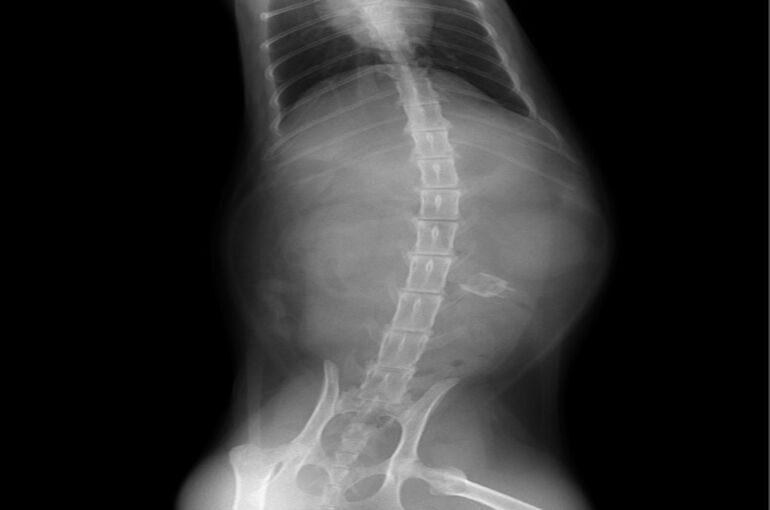

しかし2 、3日後も食欲はなく嘔吐が続いていましたので、レントゲン撮影をしたところ下記のような画像が得られました。

明らかに小腸付近に異物が検出されていましたので、当日に摘出手術を行いました。予想通り小腸にマジックのキャップのようなものが詰まっていましたので、腸を切開し摘出しました。その後は猫ちゃんは二日間入院、点滴し、食欲も戻り元気に退院していきました。